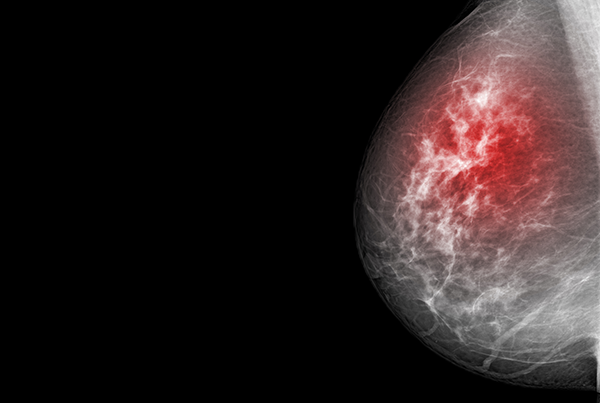

Röntgen, Szintigraphie, Strahlentherapie, Mammographie, Schilddrüsensprechstunde